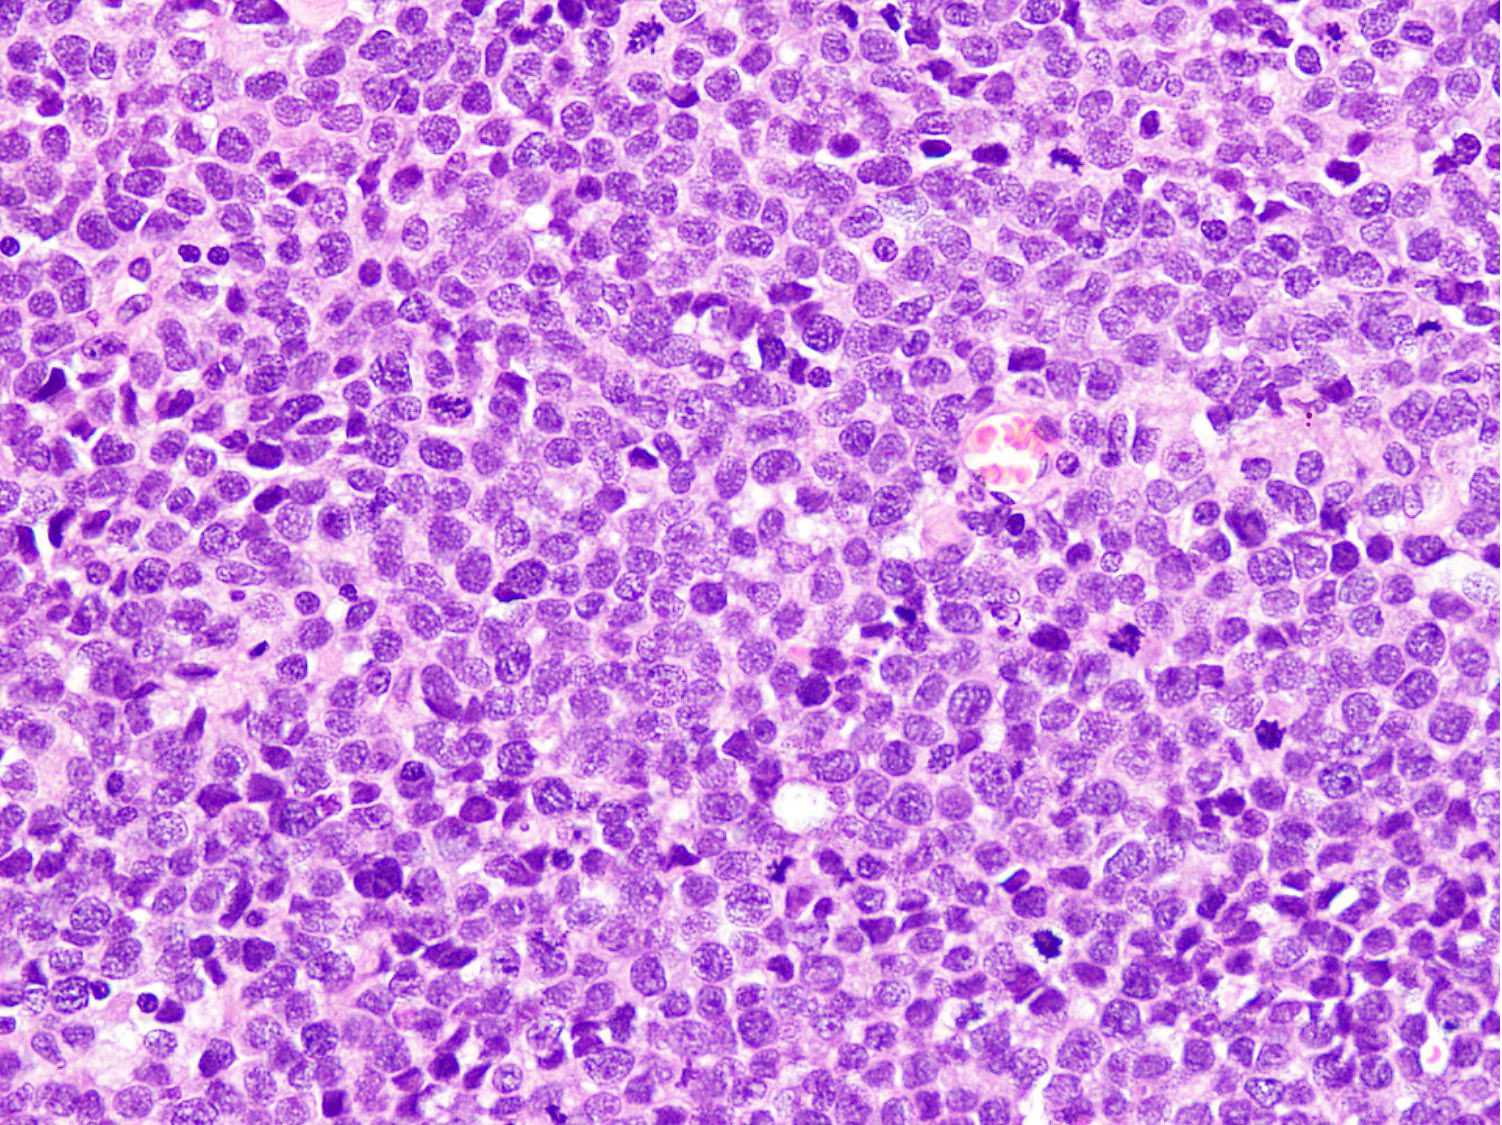

Microscopic (histologic) description

- Cellular round cell tumor

- Large clusters, nests, cords and trabeculae of primitive round cells, separated by variably thick fibrovascular septa

- Loss of cellular cohesion in the center forms alveolar-like, cystic and vague papillary appearance (Histopathology 2022;80:98)

- Layer of cells adheres to the periphery of the spaces and fibrous septa

- Small to intermediate sized monomorphic cells with scant cytoplasm

- Hyperchromatic nuclei with variable conspicuous small nucleoli

- Cells in the center have poor preservation and are necrotic; may appear floating

- Multinucleated tumor giant cells with wreath-like lineup of nuclei are common (Acta Pathol Microbiol Immunol Scand A 1982;90:345)

- Round to oval rhabdomyoblasts with abundant acidophilic cytoplasm may be present

- Brisk mitosis and variable tumor necrosis

- Occasional cases may show clear cell morphology with pale, glycogenated cytoplasm

- Rare anaplasia

- Some cases may show histologic features of embryonal rhabdomyosarcoma; molecular studies are essential to characterize such cases (Am J Clin Pathol 2013;140:82)

- Solid variant:

- Sheets of neoplastic cells

- Lack fibrovascular septa, pseudoalveolar spaces and dyscohesion (Cancer Genet Cytogenet 2005;163:138)

- May show rhabdomyoblastic differentiation

- Abundant mitotic activity

Microscopic (histologic) images

Contributed by Nasir Ud Din, M.B.B.S.